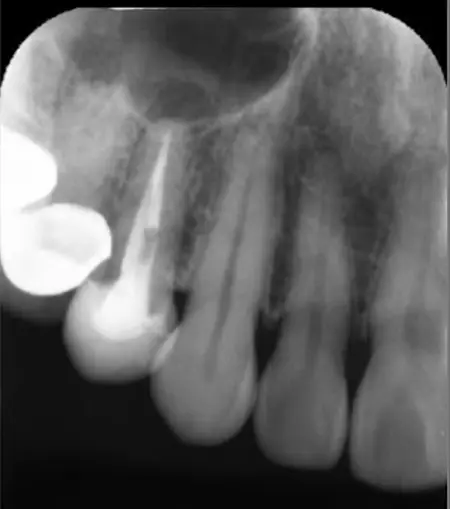

当院では、お口の中の健康とお口周りの美しさをトータル的に考えた治療を心がけています。歯科医院の目的は、虫歯・歯周病の歯の治療です。しかし最も力を入れるべきことは、虫歯や歯周病にならないための予防指導だと考えます。 プラークコントロールや歯の健康診断を定期的に受けることで大切な歯を守れるのです。丈夫で健康な歯は、何でも美味しく食べることができ、いつまでも若々しい口元と笑顔を保てます。当院の指導で、ご自分の歯で末永く健康にいきいきお過ごしいただきたいと思っています。